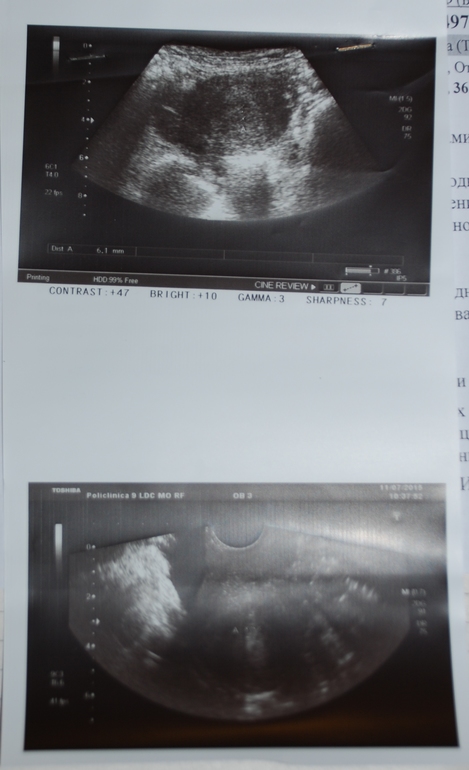

а вот это третье, июль 2015г, самое последнее. После него мне выписали циклодинон на 6 мес. с контрольным узи в ноябре: